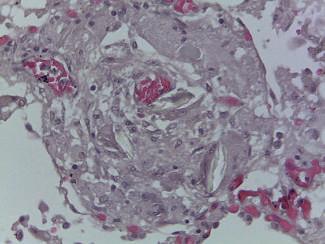

Identificação Genética de Desconhecidos

Palavras-chave: identificação humana; indivíduos não identificados; genética.

Keywords: human identification; unidentified individuals; genetics.

Introdução

A identificação de um indivíduo desconhecido, no âmbito médico-legal e forense, pode ser realizada por diversos mé todos científicos, de entre os quais destacamos a identifi cação genética, que, por regra, só é ordenada ou requerida quando nenhum dos outros métodos disponíveis possibili tou a identificação do indivíduo. Por este motivo e porque as situações que possam envolver um número de vítimas muito alargado são de reduzida ocorrência, em termos quantitativos, as perícias de identificação genética de des conhecidos não se encontram no topo das perícias mais realizadas no âmbito médico-legal e forense. Aliás, na his tória contemporânea de Portugal, o único desastre de mas sa que envolveu um número considerável de vítimas, que tiveram de ser identificadas recorrendo à identificação ge nética, ocorreu em 2017, ficando conhecido na história de Portugal como os incêndios de Pedrógão Grande. Não obs tante a casuística pouco expressiva em termos numéricos, nas primeiras décadas do corrente século XXI, o recurso às perícias de identificação genética tem-se generalizado a ní vel mundial em todas as situações de desastres de massa, chamando a si um papel de extrema importância quer em termos socias, quer em termos humanitários.

Neste capítulo abordamos o âmbito de aplicação da iden tificação genética, bem como os diferentes tipos de amos tras estudados no âmbito destas perícias, os marcadores genéticos utilizados, a valorização estatística dos resulta dos genéticos, as diferentes metodologias laboratoriais dis poníveis e, finalmente, alguns dos casos de identificação genética de especial relevância e interesse histórico.

A abordagem que fazemos à temática da identificação ge nética de desconhecidos tenta utilizar linguagem e nível de complexidade que permita a sua compreensão e, portanto, a sua utilidade, quer para académicos quer para profissio nais, quer sejam das áreas das ciências jurídicas e ciências sociais e humanas, quer sejam das áreas das ciências da vida e ciências médicas.

60.1

Identificação humana

Cada ser humano constitui-se com origem num suporte biológico que se sustenta com uma estrutura psíquica, ao qual as condições histórico-socioculturais em que se de senvolve vincam uma identidade. Este conjunto, que se traduz numa singularidade, numa realidade única, é assim reconhecido na relação entre indivíduos. A singularidade de cada ser humano é-lhe reconhecida pelos demais se res humanos e pela sociedade, não só durante todo o seu período de vida, mas também após a sua morte biológica. Neste alinhamento, o direito português confere a todo o ser humano, por força do princípio da dignidade da pessoa hu mana que inspirou a Constituição da República Portuguesa, o direito à identidade pessoal. Com o nascimento completo e com vida, todos os indivíduos adquirem simultaneamente a personalidade jurídica e inerentemente o direito à identi dade pessoal. Também a Declaração Universal dos Direitos Humanos, no seu artigo 6.º, estabelece que todos os indi víduos têm direito ao reconhecimento em todos os lugares da sua personalidade jurídica, e, portanto, da sua singulari dade e identidade pessoal.

Se é certo que a individualidade psíquica e sociocultural de um indivíduo pode ser moldável ao longo da sua vida, tal não se verifica, salvo situações absolutamente excecio nais, com a identidade genética que é, pois, o suporte da componente biológica de cada ser humano. À semelhança do conceito mais abrangente de identidade pessoal, a identidade genética assenta nas características de cada indiví duo, que se traduzam numa singularidade, numa realidade única e na possibilidade de reconhecimento dessa singula ridade entre diferentes indivíduos.

A identidade de um indivíduo presente aos serviços médico -legais, seja em vida seja em estado de cadáver, na grande maioria dos casos é verificada através daquilo que desig namos por identificação visual e que se baseia na compa ração de cada indivíduo que nos é presente com fotografias de documentos oficiais. No entanto, contrariamente ao que

© PACTOR 905

60

se passa com a maior parte dos indivíduos vivos ou cadá veres humanos frescos, a identificação visual não tem apli cação ou utilidade nos casos de cadáveres em avançado estado de decomposição, maioritariamente cadáveres es queletizados, em remanescentes humanos, em cadáveres recentes que apresentem mutilações, e em particular muti lações faciais, e, nem mesmo, em indivíduos vivos indocu mentados que não tenham, ou afirmem não ter, memória da sua identidade. Nestes casos, de acordo com orientações e consenso internacionais, a identificação individual mé dico-legal é realizada, sempre que possível, recorrendo à lofoscopia ou à informação médico-dentária. Ainda assim, quando nenhum destes métodos permitiu a identificação individual, a genética forense é então chamada a intervir para realização do exame pericial de identificação genética de desconhecido.

Sublinhar que, sendo os métodos de identificação indivi dual todos de natureza comparativa, a lofoscopia, relati vamente à identificação genética, tem, em princípio e na maior parte dos casos, a vantagem de ter quase sempre disponíveis dados para comparação em registos oficiais. É muito reduzido o número de situações em que um indiví duo não tem a sua impressão digital registada em arquivos oficiais. Já no que concerne a registos médico-dentários existem em número muito reduzido se comparados com os registos lofoscópicos oficiais.

Dada a necessidade de comparação, quanto menor e mais específico for o grupo que definimos e ao qual, em prin cípio, pertence o indivíduo ou remanescente humano a identificar, maior será a probabilidade de alcançarmos uma identificação individual positiva. Assim, o contributo prévio da intervenção pericial da antropologia forense, na orien tação da investigação da identidade, pode ser de grande valor. A intervenção pericial da antropologia forense desen volve-se no sentido de apurar o sexo biológico do indivíduo a quem pertencem os remanescentes humanos em estudo, bem como de estimar a sua idade aproximada à altura da morte, a sua estatura e robustez, ancestralidade ou afinida des populacionais, o tempo decorrido post mortem e, even tualmente, algumas informações de especial relevância na individualização dos remanescentes humanos bem como algumas informações no âmbito das causas e circunstân cias da morte. Com o conjunto de informação reunida em resultado da atividade pericial da antropologia forense, o grupo de indivíduos onde se poderá incluir o cadáver ou os remanescentes cadavéricos a identificar será tão reduzido quanto possível, possibilitando, desta forma, maior suces so das intervenções periciais subsequentes, sejam elas da medicina dentária forense sejam elas da genética forense (Amorim, Afonso-Costa, et al., 2011).

A identificação genética de desconhecidos, como já des crito anteriormente, por norma, só é ponderada quando nenhum dos restantes métodos científicos de identificação

médico-legal humana permitiu identificar o cadáver ou os remanescentes cadavéricos. Para este alinhamento con correm essencialmente dois fatores. Por um lado, o facto da identificação genética ser dos métodos periciais mais complexos e mais laboriosos e, por outro lado, o facto da identificação genética ser dos exames periciais mais dis pendiosos em termos de recursos financeiros. Mais ainda, e nesse aspeto não trazendo qualquer diferença ou vanta gem relativamente aos restantes métodos de identificação médico-legal humana, a realização das perícias de identifi cação genética de desconhecidos só é possível se existir um referencial para comparação, seja este uma amostra de referência do suposto indivíduo a identificar colhida an tes da sua morte, sejam objetos pessoais utilizados antes da morte pelo suposto indivíduo a identificar, sejam estes ascendentes diretos, descendentes diretos ou familiares com outros graus de parentesco biológico relativamente ao suposto indivíduo a identificar que concordam de forma livre e informada em ceder amostras biológicas suas para utilização no âmbito da identificação genética de um ca dáver desconhecido a identificar, sendo, aliás, esta última situação o referencial mais frequentemente utilizado, se não mesmo o único possível, no âmbito das perícias de identifi cação genética de desconhecidos realizadas pelos serviços médico-legais.

De há mais de 20 anos a esta parte, a identificação gené tica de desconhecidos, sob responsabilidade dos serviços médico-legais e forenses, concretiza-se através da deter minação do perfil genético do cadáver ou remanescentes cadavéricos a identificar, perfil este que se constitui como o conjunto de informação em determinado número, grupo ou painel de marcadores genéticos, observada no genoma do indivíduo ou remanescentes a identificar.

Existem recomendações científicas internacionais no âm bito das perícias de identificação genética de desconheci dos, relativas a várias matérias, das quais destacaríamos as recomendações relativas às qualificações mínimas dos peritos que realizam as perícias e as recomendações rela tivas aos marcadores genéticos a utilizar na realização de perícias de identificação genética de desconhecidos.

Quanto às qualificações mínimas dos peritos responsáveis por perícias de identificação genética, de acordo com a au toridade internacional competente para a área, a International Society for Forensic Genetics (ISFG), as perícias de identificação genética, aliás como quaisquer outras perícias inseridas no âmbito da genética forense, deverão ser rea lizadas por indivíduos com formação universitária de du ração mínima entre cinco a seis anos, na área da genética humana ou outra área adequada ou afim, e experiência tu telada mínima de três anos, em laboratório e com supervi sor que, também estes, cumpram estas recomendações da ISFG (Morling et al., 2002).

Tratado

Legal 906

de Medicina

Quanto aos marcadores genéticos a utilizar, as recomenda ções internacionais e designadamente as recomendações da autoridade internacional com competência na matéria –European DNA Profiling Group (EDNAP) –, determinam que os marcadores genéticos a utilizar na definição de perfis genéticos no âmbito da identificação humana são os de signados STR (do inglês short tandem repeats), também conhecidos como microssatélites ou como ADN não codi ficante repetitivo em tandem. O elenco dos STR em utiliza ção em cada país, quer em termos quantitativos quer em termos qualitativos, é determinado com base em critérios técnicos e científicos rigorosos e bem definidos que, por seu lado, permitem sempre alguma flexibilidade na decisão final das autoridades políticas competentes, e designada mente no que se refere ao número de STR a utilizar.

60.2

Âmbito de aplicação

A identificação genética de desconhecidos no âmbito mé dico-legal, em regra e como já referido anteriormente, tem sempre lugar quando nenhum outro método científico de identificação humana permite identificar um indivíduo ou re manescentes humanos, podendo, no entanto, por decisão de autoridade judicial ou judiciária ou por decisão do perito médico titular do processo, ser o único método utilizado em determinadas situações em concreto, ainda que, esta segunda alternativa seja de ocorrência excecional.

A identificação genética pode ter por objeto um único indi víduo ou remanescentes humanos com origem num único indivíduo, ou remanescentes humanos com origem em múl tiplos indivíduos. O indivíduo, remanescentes humanos ou

indivíduos a identificar podem ser indivíduos vivos ou ca dáveres, sendo, no caso destes últimos, as situações mais comuns as dos cadáveres esqueletizados (Figura 60.1). Genericamente, no que se refere aos cadáveres presentes para identificação genética de desconhecidos, as situações mais frequentes na rotina pericial dos serviços médico-le gais resultam quer de mortes naturais por doença ou por outros fatores intrínsecos ao indivíduo, quer de mortes vio lentas, nas quais incluímos os suicídios, os homicídios e os acidentes, sejam estes, acidentes rodoviários, incêndios, explosões, derrocadas, naufrágios ou outros.

Quando estamos perante acidentes ou quaisquer fenó menos cuja magnitude e, sobretudo, o número de vítimas, impliquem a necessidade de assistência externa, segundo a Organização Mundial de Saúde (OMS), estamos perante situações que se classificam como desastres de massa. Os principais desastres de massa ocorridos na história da hu manidade têm resultado da ocorrência quer de catástrofes naturais, como erupções vulcânicas, tsunamis, furacões, ciclones, terramotos, inundações, secas extremas, incên dios, de entre outras, quer de acidentes de aviação, quer, ainda, de conflitos bélicos ou de outros conflitos políticos e atos terroristas, dos quais, em regra, o número de vítimas é muito elevado e o número de vítimas a submeter a perícias de identificação genética de desconhecidos pode, também, ser muito elevado.

Para além de indivíduos vivos ou cadáveres para identifica ção genética de desconhecidos no âmbito das situações até aqui elencadas, os serviços médico-legais recebem, ainda, para identificação genética, remanescentes de inter rupções de gravidez (Figura 60.2), fetos ou remanescentes fetais (Figura 60.3), recém-nascidos, bem como amostras biológicas que classificamos como amostras dúbias.

Identificação Genética de Desconhecidos 907 © PACTOR

Fig. 60.1 Corpo esqueletizado, para identificação Fig. 60.2 Remanescentes de interrupção da gravidez, para identificação do pai biológico

Quanto à identificação genética de desconhecidos que tenha lugar em amostras provenientes de remanescentes fetais ou embrionários, sublinharíamos que o artigo 42.º do Código Penal Português prevê que, após interrupção da gravidez ordenada na sequência de crime sexual de viola ção, deve ocorrer identificação genética dos remanescen tes embrionários ou fetais por comparação com a amostra do presumível agressor/pai biológico. Já no caso de na dos-vivos ou mortos em que tenha ocorrido o abandono, a identificação genética tem lugar com vista ao apuramento de quem terá sido a presumível responsável pelo abando no/mãe biológica.

Quanto ao que habitualmente designamos como amostras dúbias, podem ser amostras colhidas no âmbito da realiza ção de análises clínicas ou de outros exames complemen tares de diagnóstico, como exames anátomo-patológicos, e, designadamente, sangue ou fragmentos de tecidos hu manos dos mais diversos órgãos e localizações, e relativa mente às quais não há a certeza do indivíduo, da pessoa a quem pertencem, a quem se referem. As amostras dú bias podem, ainda, ser amostras colhidas não no âmbito do diagnóstico médico, mas no âmbito de exames periciais de toxicologia forense, designadamente sangue colhido em contexto de determinação de alcoolémia ou de determi nação de drogas de abuso, bem como amostras colhidas no âmbito de controlos de dopagem em atletas. Comum a todas as amostras dúbias elencadas é o facto de não exis tir, ou de ter sido levantada suspeição sobre, a verdadei ra identidade do indivíduo a quem pertence determinada amostra e, portanto, a quem ficará associado, a quem será atribuído, determinado diagnóstico médico ou a prática da utilização ilegal de determinada substância ou substâncias.

60.3

Amostras problema estudadas

Se o indivíduo a submeter a perícia de identificação genéti ca for um indivíduo vivo ou um cadáver nas condições que classificamos como cadáver fresco, as amostras biológicas

colhidas para a sua identificação podem ser sangue total em tubo ou em mancha de sangue (Figura 60.4) ou raspado da mucosa oral colhido em zaragatoa.

Fig. 60.4 Fotografia de mancha de sangue (amostra de refe rência), colhida em suporte de papel. Ver a cores